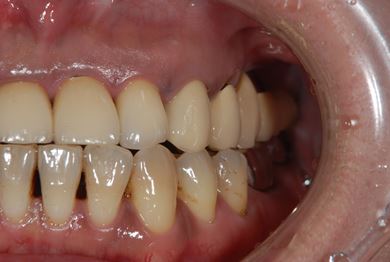

| 性別/年齢 | 女性 / 44歳 | ||||||||||||||||||||||||||||||||

| 主訴 | 上のさし歯がグラグラする。インプラントにした方が良いのか、相談したい。 | ||||||||||||||||||||||||||||||||

| 治療方針 | 抜歯と同時にインプラントを埋入し、治療期間を短縮する。 | ||||||||||||||||||||||||||||||||

| 治療内容 | インプラント2本(抜歯即日スピードインプラント)、メタルボンドセラミック2本 | ||||||||||||||||||||||||||||||||